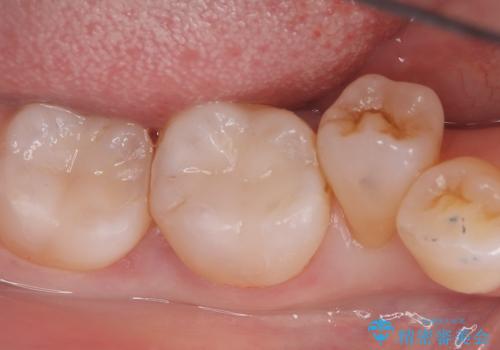

下顎大臼歯部に入っている保険適用のメタルインレーを、適合性と審美性の良いセラミックインレーでのやり替えとなりました。

セラミックインレーセット時はラバーダム防湿を行っています。